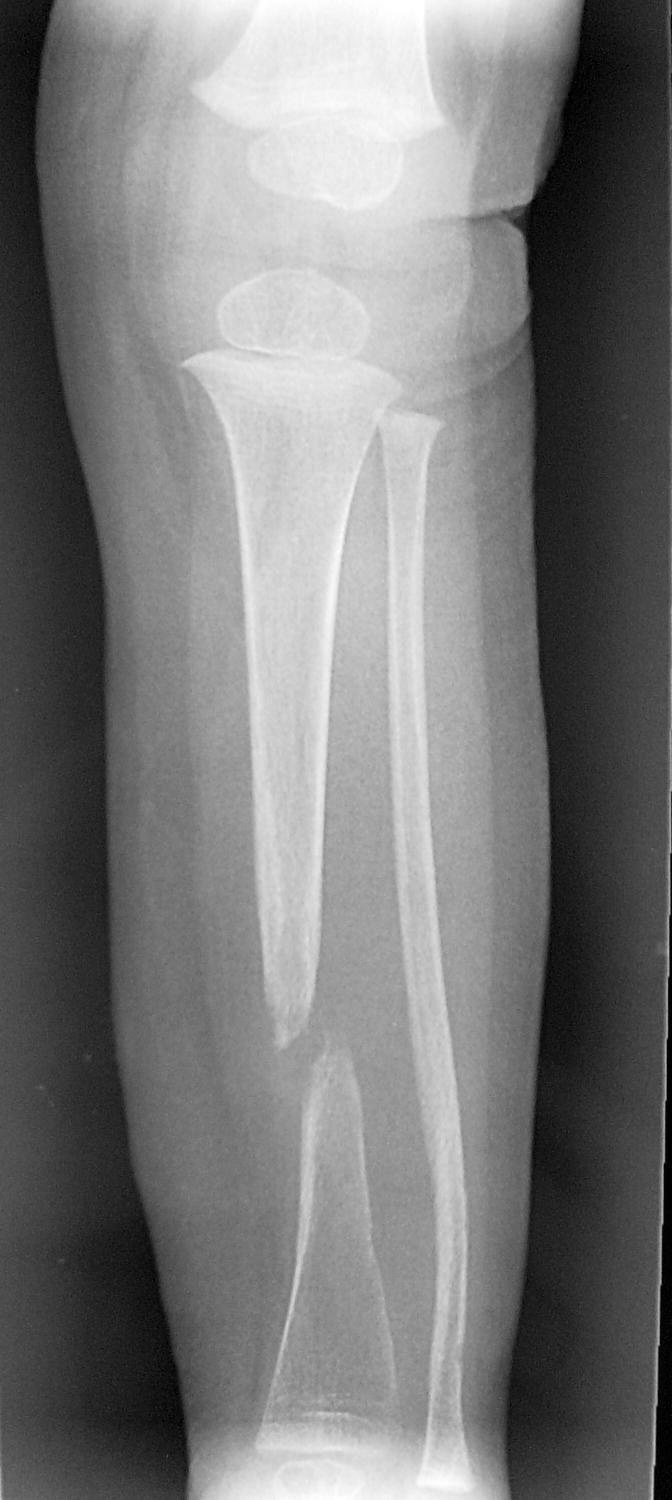

Identify the disease & the associated pathologic finding:

COLA1

Osteogenesis imperfecta

Olecranon avulsion fracture